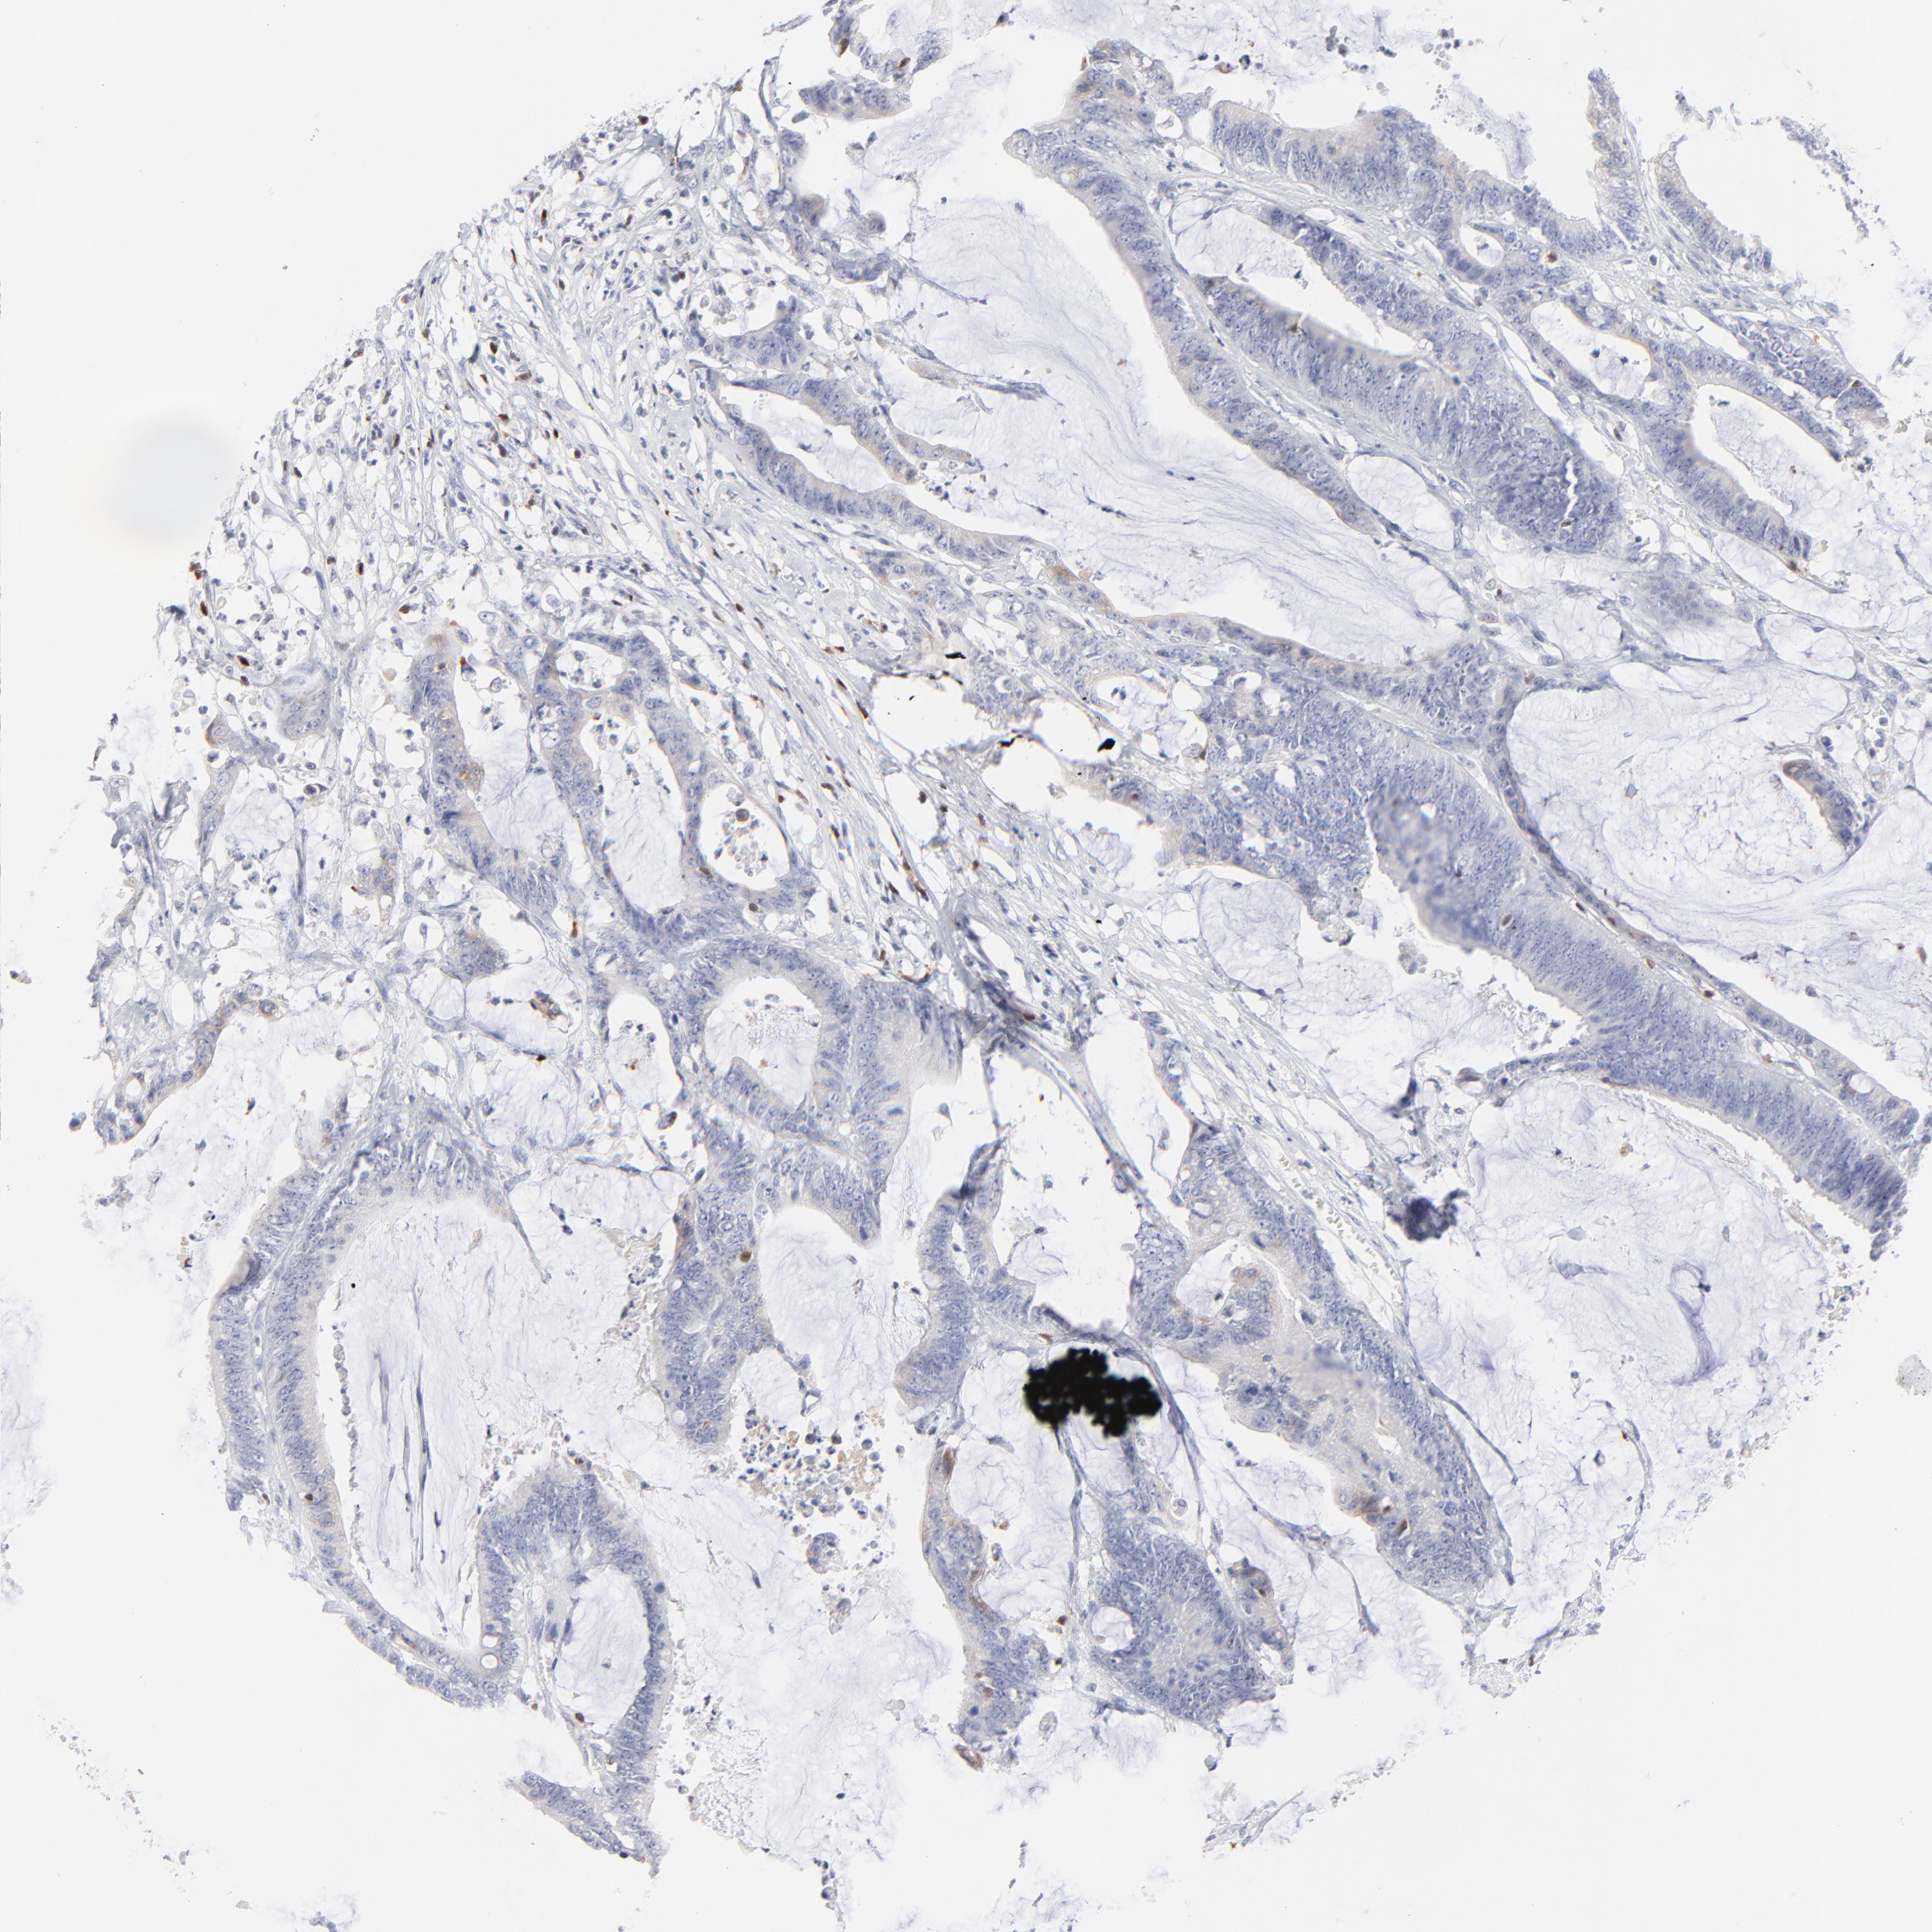

CANCER COLORECTAL CANCER Show tissue menu

Colorectal cancer

Human cancer